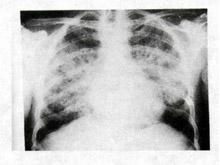

PCP肺炎PCP好發於免疫缺陷的兒童和成年人,偶發生於健康人。本病的主要臨床特點為大多數病人有發熱、呼吸困難和紫紺及乾咳等,僅根據臨床表現不易診斷。PCP胸片的典型改變為雙側瀰漫性肺泡和間質浸潤,開始由肺門向外擴展,隨之迅速實變為蝶狀陰影,肺尖和肺底很少累及。分析13例PCP的X線特點,歸納為4種形態:(1)間質肺泡浸潤;(2)輕度瀰漫性肺泡滲出;(3)中度融合性肺實變;(4)重度瀰漫性肺實變。

其他輔助檢查:X 線表現是非特異性的,10%~25%患者胸部X 線可正常。典型的X 線表現為瀰漫性肺間質浸潤,以網狀結節影為主,由肺門向外擴展。病情進展,迅速發展為肺泡實變,病變廣泛而呈向心性分布,與肺水腫相似。在實變病灶中雜有肺氣腫和小段不張,以肺的外圍最明顯。罕有氣胸或胸腔積液等胸膜病變。亦有以局限性結節陰影,單側浸潤為表現。肺功能檢查肺活量減低,肺彌散功能(DLCO)低於70%估計值。

PCP肺炎肺部X線檢查:

可見雙肺從肺門開始的瀰漫性網狀結節樣間質浸潤,有時呈毛玻璃狀陰影,一般不累及肺尖、肺底和肺外帶;有時可見肺部局限性結節陰影、大葉實變、空洞、肺門淋巴結腫大、胸水等,但多數患者合併細菌或真菌感染,X線檢查多不典型。